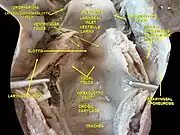

Middle pharyngeal constrictor muscle Deep dissection of larynx, pharynx and tongue seen from behind

Deep dissection of larynx, pharynx and tongue seen from behind Deep dissection of larynx, pharynx and tongue seen from behind

Deep dissection of larynx, pharynx and tongue seen from behind Deep dissection of larynx, pharynx and tongue seen from behind

Deep dissection of larynx, pharynx and tongue seen from behind